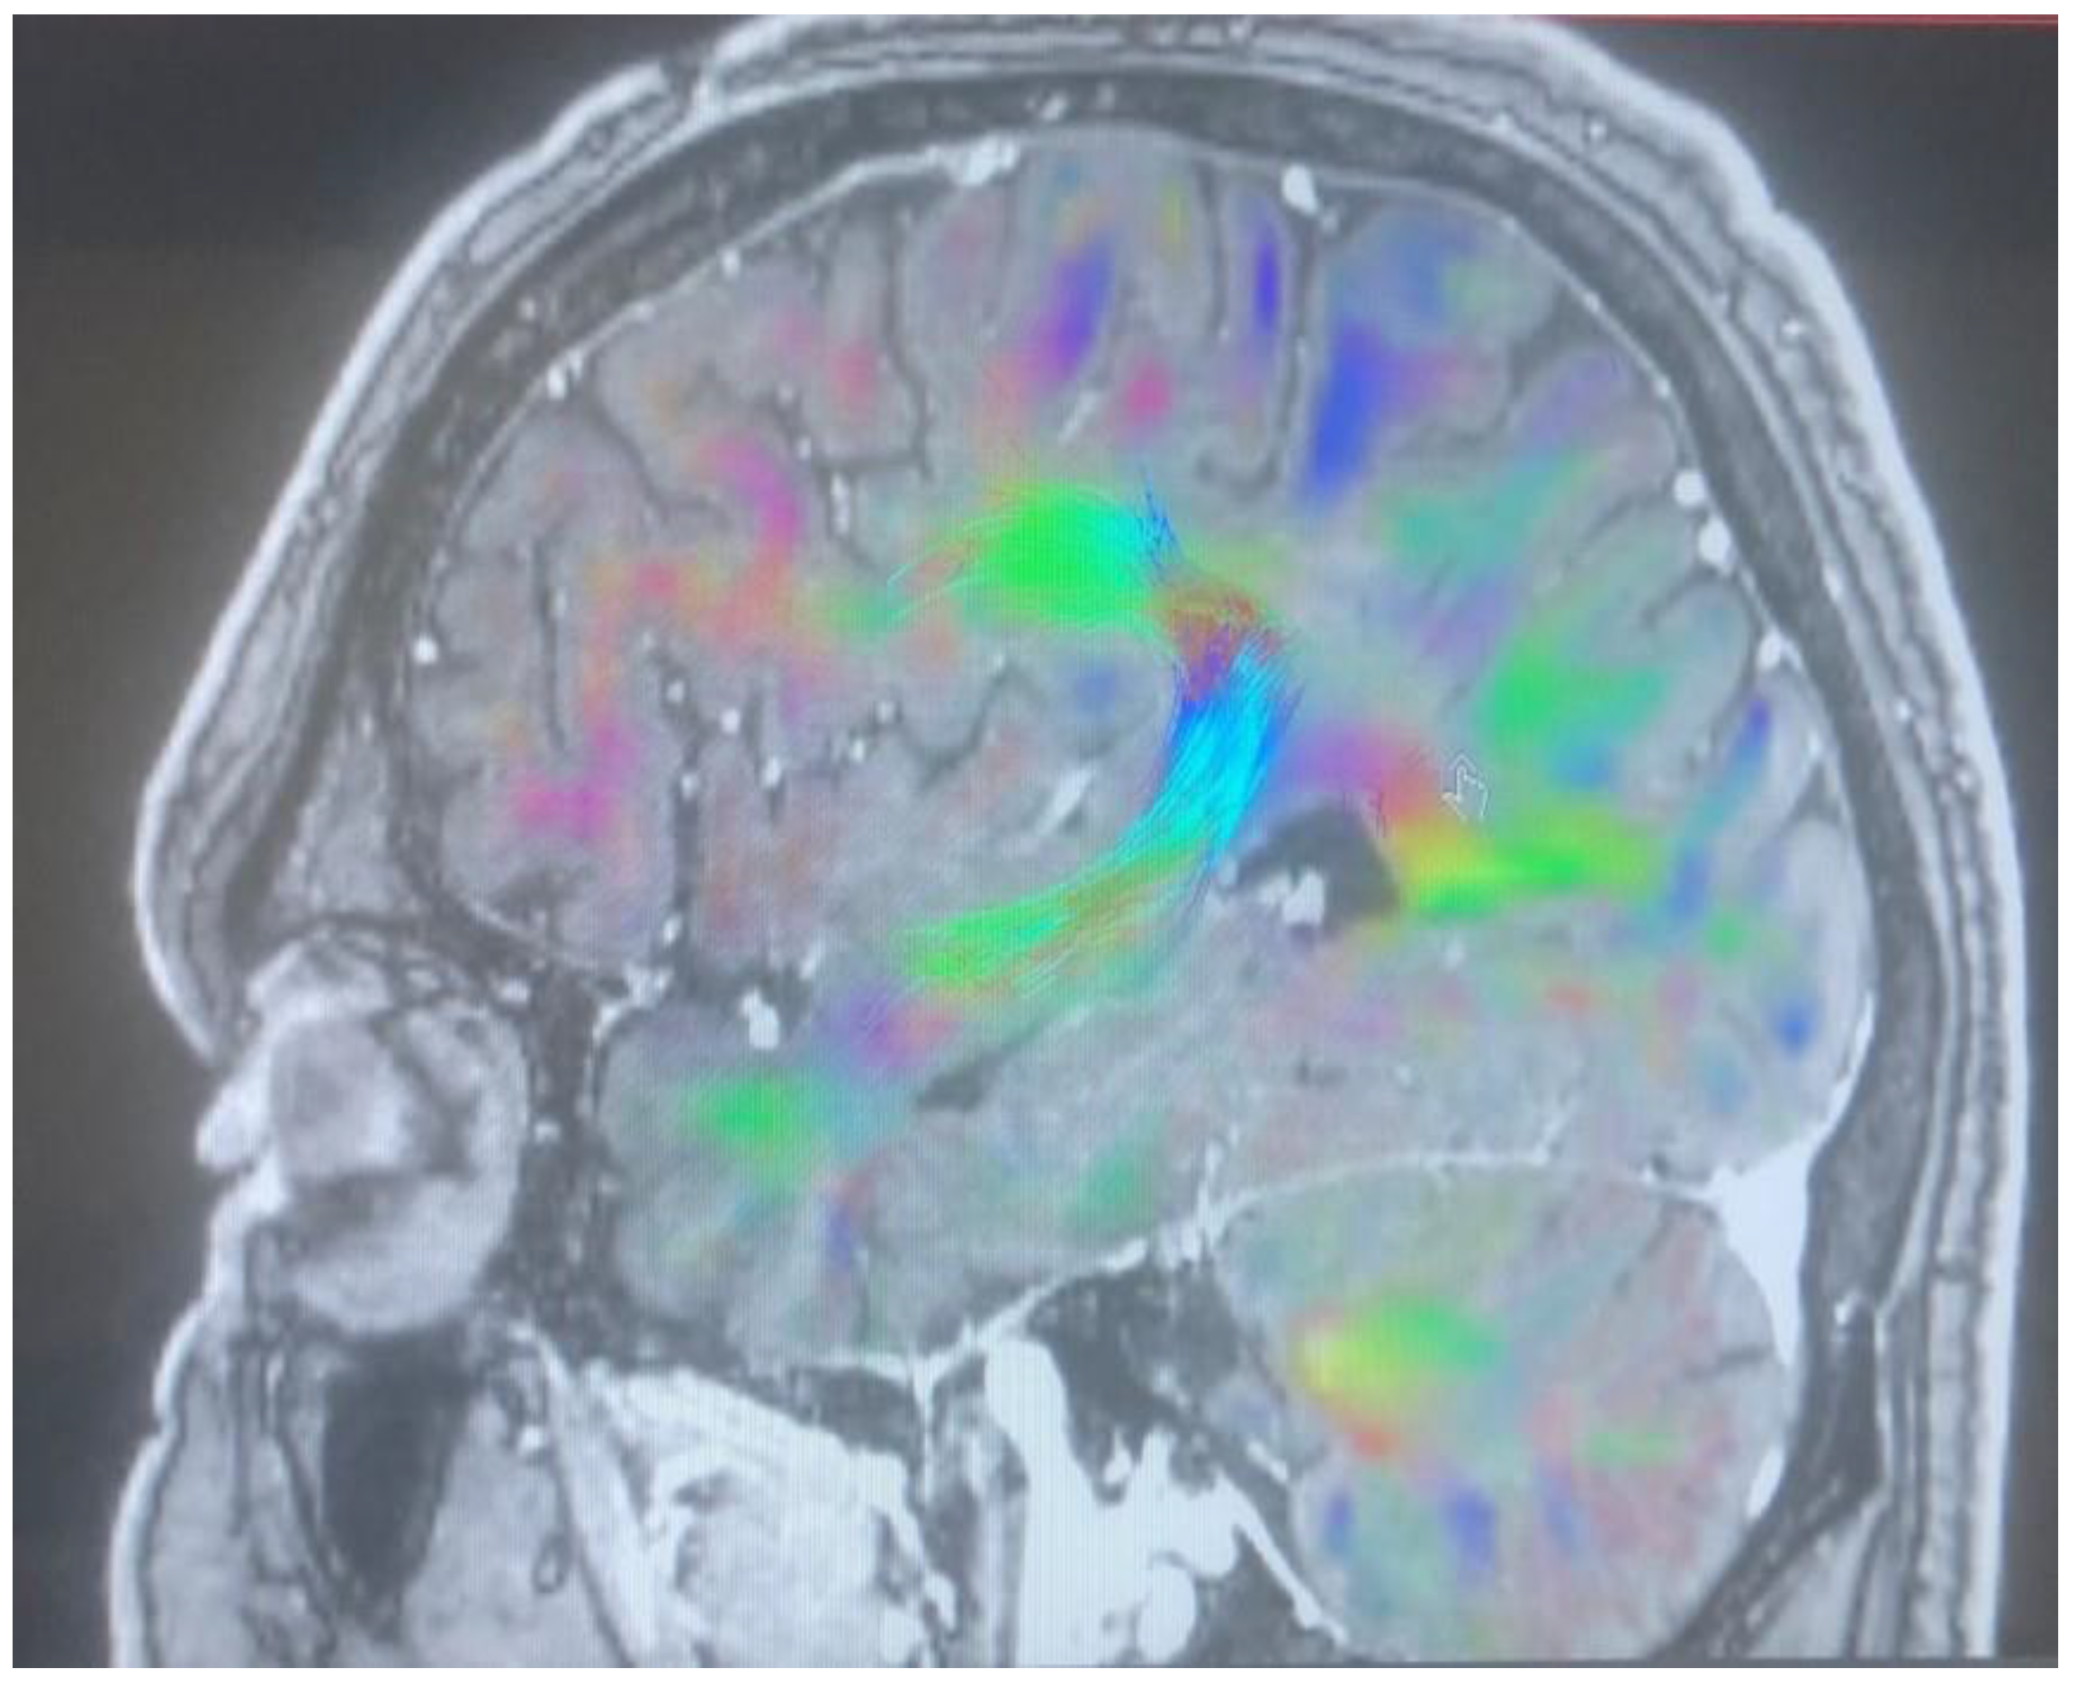

Changes in the anatomy of forceps minor before and after cingulotomy are presented in Figure 2 and Figure 3; moreover, arcuate fasciculus before and after cingulotomy is presented in Figure 4 and Figure 5.

Figure 4. Arcuate fasciculus before cingulotomy.

Brainsci 13 00044 g004